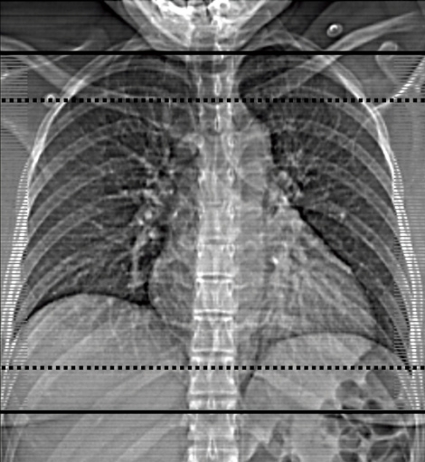

Lungröntgen. Det går inte att med lungröntgen vare sig specifikt påvisa LE eller skilja mellan ischemiska och pneumoniska parenkymförtätningar [44]. Undersökningen kan dock vara av värde för differentialdiagnostik (till exempel pneumotorax, massiv pleurautgjutning och lungödem) innan man går vidare med DTLA och för bedömning av skintigrafi [3, 7, 45, 46]. Lungröntgen ger minimal stråldos till både moder (medeltal Sverige 2006: 0,07 mSv) [47] och foster (<0,01 mGy) [32]. Lungskintigrafi. En systematisk litteraturgenomgång år 2006 avseende bilddiagnostik av LE hos gravida [9] fann endast en retrospektiv skintigrafistudie [48] som motsvarade de uppsatta kvalitetskriterierna med bland annat uppföljning av patienter med negativt test. Ytterligare en retrospektiv skintigrafistudie (n = 97) publicerades 2007 [49]. Skintigrafifynden i dessa två studier bedömdes som normala hos 172 (81,9 procent), icke-diagnostiska hos 35 (16,7 procent) och förenliga med hög sannolikhet för LE hos 3 (1,4 procent) patienter. Sex kvinnor med normalt (n = 2) eller icke-diagnostiskt (n = 4) fynd fick antikoagulationsbehandling på klinisk grund. Övriga med icke-diagnostisk (n = 31) eller normal (n = 170) skintigrafi hade ingen episod av VTE under 20–25 månaders medeluppföljning. Icke konklusiva skintigrafifynd vidareutreds i första hand med DTLA. Om inte heller DTLA är konklusiv görs ultraljud avseende DVT i nedre extremiteterna. Ett normalt bilateralt ultraljud av hela benet, eller seriellt proximalt ultraljud dag 1, 3 och 7 i kombination med icke-diagnostisk skintigrafi, utesluter med hög sannolikhet behandlingskrävande VTE hos icke-gravida [3]. I tidig graviditet är det viktigt att vara medveten om ökad förekomst av DVT i övre extremiteter och v jugularis i samband med assisterad befruktning [50]. Skintigrafi utförs på de flesta av landets sjukhus med konventionell planar teknik, ofta tolkad utifrån reviderade probabilistiska kriterier [51] byggda på PIOPED I-studien (prospective investigation of pulmonary embolism diagnosis), och med relativt hög andel icke konklusiva undersökningar [52]. Med modern skintigrafi (SPECT, single photon emission tomography) kan antalet icke konklusiva undersökningar reduceras till 1–3 procent [53-55]. I nya rekommendationer för diagnostik av LE föreslås SPECT vara förstahandsmetod också för gravida [21, 22]. Enligt dessa och andras rekommendationer [7, 19, 20] utförs skintigrafi hos gravida primärt endast med perfusion och med reducerad aktivitet (cirka 50 MBq), oavsett om planar skintigrafi eller SPECT används. I de relativt få fall som perfusionsskintigrafin är patologisk kompletteras med ventilationsskintigrafi nästa dag för att säkerställa diagnosen. Datortomografi av lungartärer. Hos icke-gravida, men inte hos gravida, finns evidens för att normal DTLA med hög säkerhet utesluter behandlingskrävande VTE [56, 57]. Nyligen publicerades två artiklar som uppmärksammade kända brister i diagnostisk kvalitet för DTLA hos gravida [13, 15], vilka huvudsakligen berodde på för låg kontrasttäthet i lungartärerna sekundärt till ökad hjärtminutvolym [58] under graviditet [59]. Man kan alltså inte använda injektionsprotokoll för icke-gravida på gravida. Gravida kräver högre kontrastmedelsdoser och/eller injektionshastigheter [14]. Analys visar att med studiernas [13, 15] injektionsparametrar varierade doshastigheten mellan 15 och 23 mg jod per kg och sekund vid en vikt på 60–80 kg. Enligt vår erfarenhet krävs det cirka 30 mg jod per kg och sekund på gravida för att kontrasttätheten i lungartärerna ska bli tillräcklig (Figur 1, Tabell V). Patienten bör noga instrueras att hålla andan utan valsalvamanöver och undvika djup inandning [14, 60]. MRT av lungartärerna har i dag ingen etablerad plats i diagnostiken av LE. Sammanfattning Evidens saknas angående val av bästa strategi vid diagnostik av LE hos gravida. Vid val av bilddiagnostisk metod måste man vid varje sjukhus ta hänsyn till tillgänglig metodik, expertis, lokala erfarenheter och vilken diagnostisk kvalitet och stråldos metoderna levererar. Strålsäkerhetsmyndigheten föreskriver specifikt för gravida att de »ska undersökas med utrustning och metod som ger en så låg stråldos till fostret som är rimligt möjligt. Valet skall dock göras så att den nödvändiga diagnostiska informationen erhålls« (SSMFS 2008:31). Skillnader i stråldos mellan skintigrafi med halverad aktivitet och DTLA är enligt Tabell IV större för modern än för fostret. Risken för strålinducerad letal cancer är störst för modern efter DTLA även om stråldoserna vid DTLA optimeras enligt förslag i Tabell V. Risken med stråldoserna vid skintigrafi och DTLA för den enskilda modern och fostret måste dock anses som negligerbar jämfört med konsekvenser av både under- och överdiagnostik av LE. Vi rekommenderar perfusionsskintigrafi (halverad aktivitet) som förstahandsmetod för diagnostik av LE hos gravida på grund av hög andel konklusiva undersökningar, lägre stråldos till modern (speciellt till den proliferativa bröstvävnaden, som kan vara extra känslig för joniserande strålning under graviditet och särskilt vid kända riskfaktorer för att utveckla bröstcancer), inga kontrastmedel och viss osäkerhet vad gäller DTLA:s diagnostiska kvalitet [61]. Vid misstanke om LE hos unga icke-gravida kvinnor kan skintigrafi också vara att föredra som förstahandsmetod på grund av den lägre stråldosen till bröstkörtlarna. Varje sjukhus bör ha en dokumenterad utredningsplan för gravida med misstänkt LE, och man bör optimera stråldoserna vid skintigrafi och DTLA samt kontrastmedelsprotokollen vid DTLA. Varje gravid kvinna ska ha rätten att få korrekt information om typ och magnitud av potentiella risker som hon själv och fostret kan bli utsatt för. Kortvarig behandling med lågmolekylärt heparin kan vara indicerad om önskad metodik/expertis tillfälligt saknas. Man kan avvakta med objektiv diagnostik 1–2 två dygn efter påbörjad behandling utan att riskera att kliniskt signifikanta lungembolier helt löses upp. Det pågår två prospektiva multicenterstudier som förhoppningsvis ska bringa mer klarhet i diagnostiken av LE hos gravida [9]. I den ena studien (Kanada) består den diagnostiska strategin i klinisk sannolikhetsbedömning, ultraljud och skintigrafi. I den andra studien (Holland) används DTLA som primär och enda metod för att diagnostisera LE samtidigt som också D-dimer utvärderas [42]. * Ulf Nyman, Henry Eriksson och Margareta Hellgren-Wångdahl ingick i SBU:s projektgrupp och Socialstyrelsens arbetsgrupp för diagnostik av venös tromboembolism. Marika Bajc och Björn Jonson ingick i arbetsgruppen inom European Association for Nuclear Medicine för utarbetande av europeiska riktlinjer för lungembolidiagnostik. Håkan Geijer är vice ordförande i Svensk förening för nuklearmedicin. * Bibliotekarie Elisabeth Sassersson har hjälpt till att ta fram all litteratur.